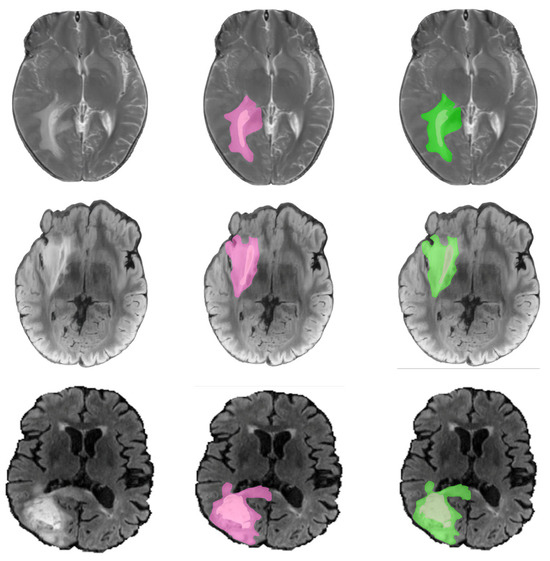

Improving Brain Tumor Detection by Cortical Surface and Vessels Segmentation Through RGB-to-HSI Transfer Learning

by Guillermo Vazquez, Alberto Martín-Pérez, Angel Perez-Nuñez, Alfonso Lagares, Eduardo Juarez and Cesar Sanz

Cancers 2026, 18(5), 857; https://doi.org/10.3390/cancers18050857 - 6 Mar 2026

Background: Accurate in vivo brain tumor detection using hyperspectral imaging (HSI), a non-invasive technique that captures spectral information beyond the visible range, is challenging due to the complexity of biological tissues and the difficulty in distinguishing malignant from healthy areas. Conventional neural-network-based methods often misclassify tumor tissue as blood vessels, largely due to high vascularization and the scarcity of annotated data. Method: To address this issue, this work proposes an underexplored approach that decomposes the problem into two tasks: (1) segmentation of the brain cortical surface and its blood vessels, and (2) segmentation of biological tissues within the segmented craniotomy site. The cortical segmentation task is addressed independently of the segmentation model used in the second stage. To achieve this, a set of pseudo-labels is generated from RGB and HSI captures acquired during in vivo brain surgeries. These pseudo-labels support a multimodal training strategy that leverages both imaging domains, yielding a model capable of segmenting the craniotomy site and the blood vessels contained in it. The model is further refined on HSI using weakly supervised fine-tuning with sparse ground truth annotations. Results: The final segmentation map combines cortical and tissue segmentation outputs, considering only cortex pixels not overlapped by vessels as potential tumor regions. This simplifies the HSI tissue segmentation task, reframing it as a binary segmentation of healthy vs. other tissues, while still enabling a comprehensive multiclass output. Conclusions: The proposed method achieves up to a 15.48% increase in F1 score for the tumor class, while segmenting the brain cortex with a mean Dice similarity coefficient (DSC) of 92.08% and accurately detecting 95.42% of labeled blood vessel samples in the HSI dataset. Full article